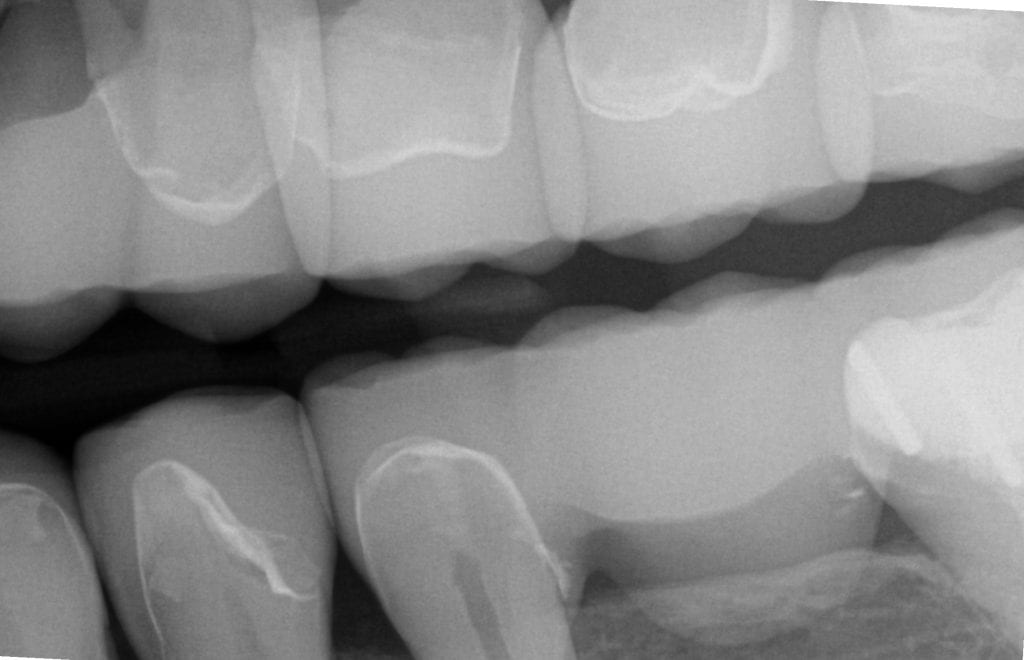

ONE WEEK POST-OP RADIOGRAPHS / CEMENT CHECK